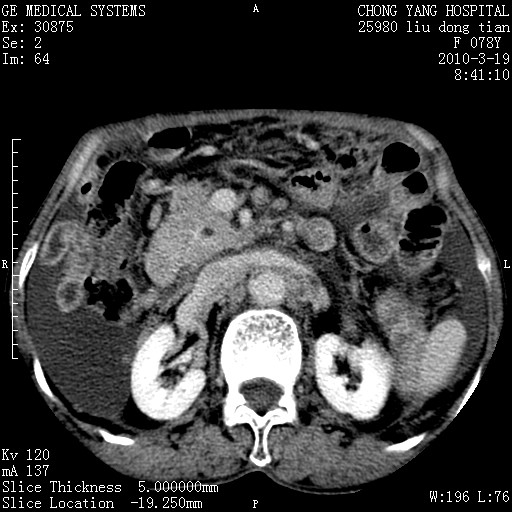

标题: CT25199:F 78Y 腹胀半年 消瘦乏力 [打印本页]

胆囊壁增厚并明显强化,胆囊癌伴多发转移瘤可能性大,淋巴瘤不除外,右肾囊肿,胸腹水.

考虑nhl,肝、脾、腹膜腔及腹膜后多发淋巴结受侵,腹水,右肾囊肿,慢性胆囊炎,右侧少量胸腔积液。

首先考虑恶性淋巴瘤 。

胰头有肿块形成,胰头ca伴肝脾、腹膜腹膜后转移

胆囊有软组织影有强化,支持胆囊癌,肝脾、腹膜后淋巴结转移。

nhl的淋巴结多围绕主动脉,而且主动脉会移位,所以不考虑nhl。

分开来讲:肝左叶、尾叶病灶有不均强化像肝癌;

脾脏病灶无强化,像多发囊肿或淋巴管瘤,不除外淋巴瘤(低强化);

胆囊增生性病变:胆囊癌,腺肌增生症,慢性胆囊炎;

肝门、胰腺头、腹膜后多个团块: 淋巴瘤,转移;

腔静脉肝内段细小有无布加可能?

一元论最好了 淋巴瘤所致改变; 胆囊癌转移不像,胆囊周围肝组织清晰,肝癌淋巴结转移?三元论都不止。

胰头ca伴肝脾、腹膜腹膜后转移!

最后报的胰头癌多发转移,脾脏单独考虑囊肿或淋巴管瘤。